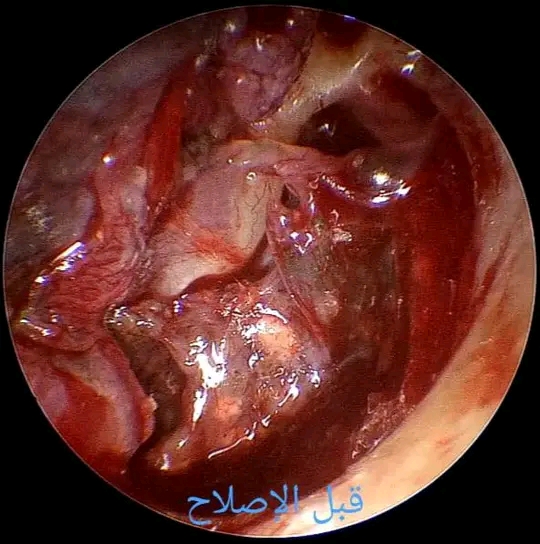

وأوضح الدكتور مجدي القاضي عميد كلية الطب البشري ورئيس مجلس ادارة المستشفيات الجامعية انه تم فحص المريض بوحدة السمعيات واجريت له اشعة مقطعية لعظام الاذن بقسم الاشعة ثم تقرر التدخل الجراحي باستخدام منظار الاذن الوسطى، وهي إحدى التقنيات الدقيقة والمتقدمة المتوفرة بالقسم.

وأضاف الدكتور احمد كمال عبد الحميد المدير التنفيذي للمستشفيات الجامعية ان العملية تمت بنجاح باستخدام المنظار وهو ما يمثل تطورا مهماً في جراحات الاذن الدقيقة، مشيرا الى ان الفريق الطبي تعامل باحترافية عالية مع الحالة المعقدة وحقق نتائج مبشرة.

وقال الدكتور محمد عبدالغفار رئيس قسم الانف والاذن والحنجرة ان خلال العملية التي تمت تحت التخدير الكلي لاستكشاف الاذن الوسطى، تم العثور على أجسام غريبة متمثلة في شظايا، بالاضافة الى وجود التصاقات وانفصال تام بين عظيمات الاذن الدقيقة، وقد تمكن الفريق الطبي من استخراج الشظايا وفك الالتصاقات، واعادة توصيل العظيمات بكفاءة عالية باستخدام المنظار مما يتيح للمريض استعادة القدرة السمعية بدرجة كبيرة.